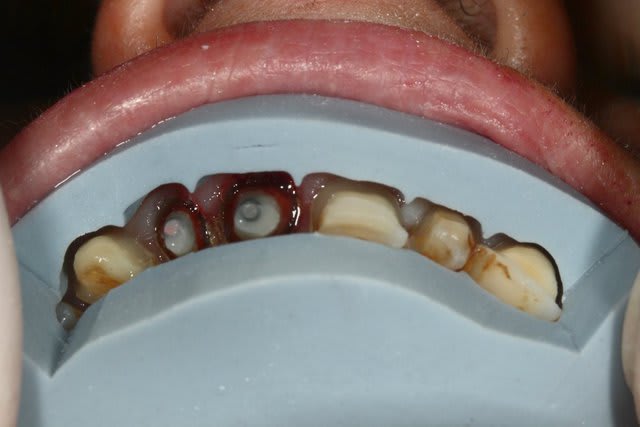

Tu as des photos en occlusal ?

Avant d'envisager la moindre facette, il va falloir je pense revoir l'occlusion de ta patiente: courbe de Spee foirée à gauche, parafonction 21,22, vestibulo-version 12 suite DDM inf.

Après pour la partie technique pure au niveau antérieur, tout dépend de l'état d'usure palatine, et de lq stabilisation du bruxisme/parafonction, (comme demandé plus haut par GP) une photo occlusale peut nous guider pour connaître la meilleur thérapeutique à adopter, et l'éventail est large: du simple composite à la couronne périphérique en passant par la facette bilaminaire (au fait Gp se serait sympa de partager ce genre de cas avec les Nonoliens ;-)).

Ma question est purement technique. En palatin on ne note pas d'usure. Comment gérer la profondeur à rattraper, sur 23 par exemple, et comme tu l'indiques, Cingulum, quid de la qualité du collage sur ce type de dentine sclérosée? Avez-vous des trucs et/où astuces ?